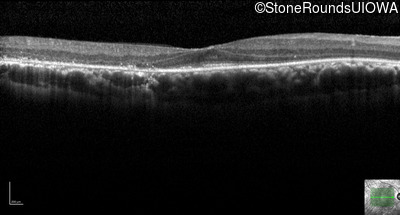

Age at visit: 62 years

OD OS

This 62 year old man had poor night vision as a teenager and developed difficulty with his peripheral vision in his early forties. His parents both grew up in the small village in Taiwan.